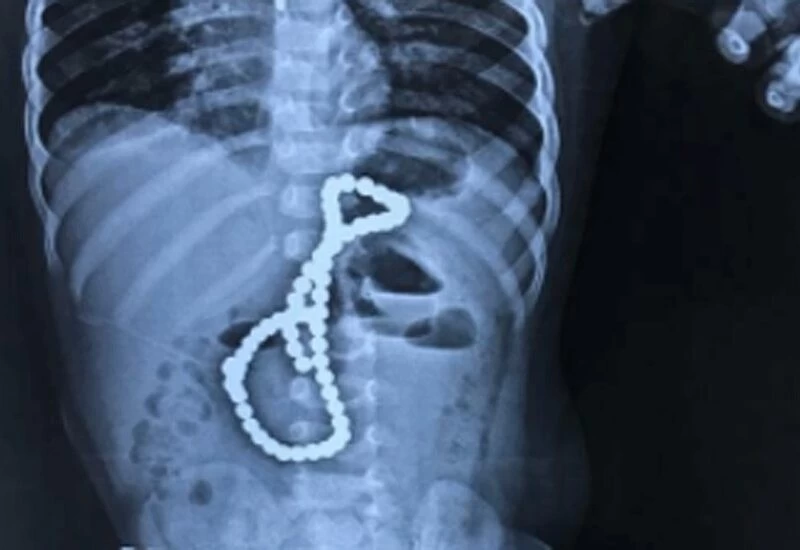

लखनऊ में एक डेढ़ साल के बच्चे ने खेलते समय एक-एक करके मैग्नेट की 65 गोलियां निगल लीं। 5 घंटे के सफल ऑपरेशन के बाद डॉक्टरों ने सभी गोलियां निकाल लीं और बच्चे की जान बचा ली। बच्चा अब पूरी तरह से ठीक है। बच्चे को लगातार उल्टी और निर्जलीकरण की शिकायत थी। डॉक्टरों ने तुरंत एक्स-रे करवाया। एक्स-रे में, डॉक्टरों ने पेट में एक माला की तरह कुछ दिखाया। बच्चे के परिवार ने घर पर इस तरह की माला होने से इनकार किया। इलाज के लिए डॉक्टर ने ऑपरेशन के लिए परिवार से बात की।

अस्पताल के एचओडी डॉक्टर एडेरा खान ने कहा कि पेट से एक के बाद एक करके मैग्नेट की 65 गोलियां निकालना सबसे बड़ी चुनौती थी। गोलियाँ एक साथ चिपक कर एक माला का रूप ले लीं। 5 घंटे के सफल ऑपरेशन के बाद, डॉक्टरों ने बहुत सावधानी से बच्चे के पेट से चुंबक की गोलियां निकाल दीं।